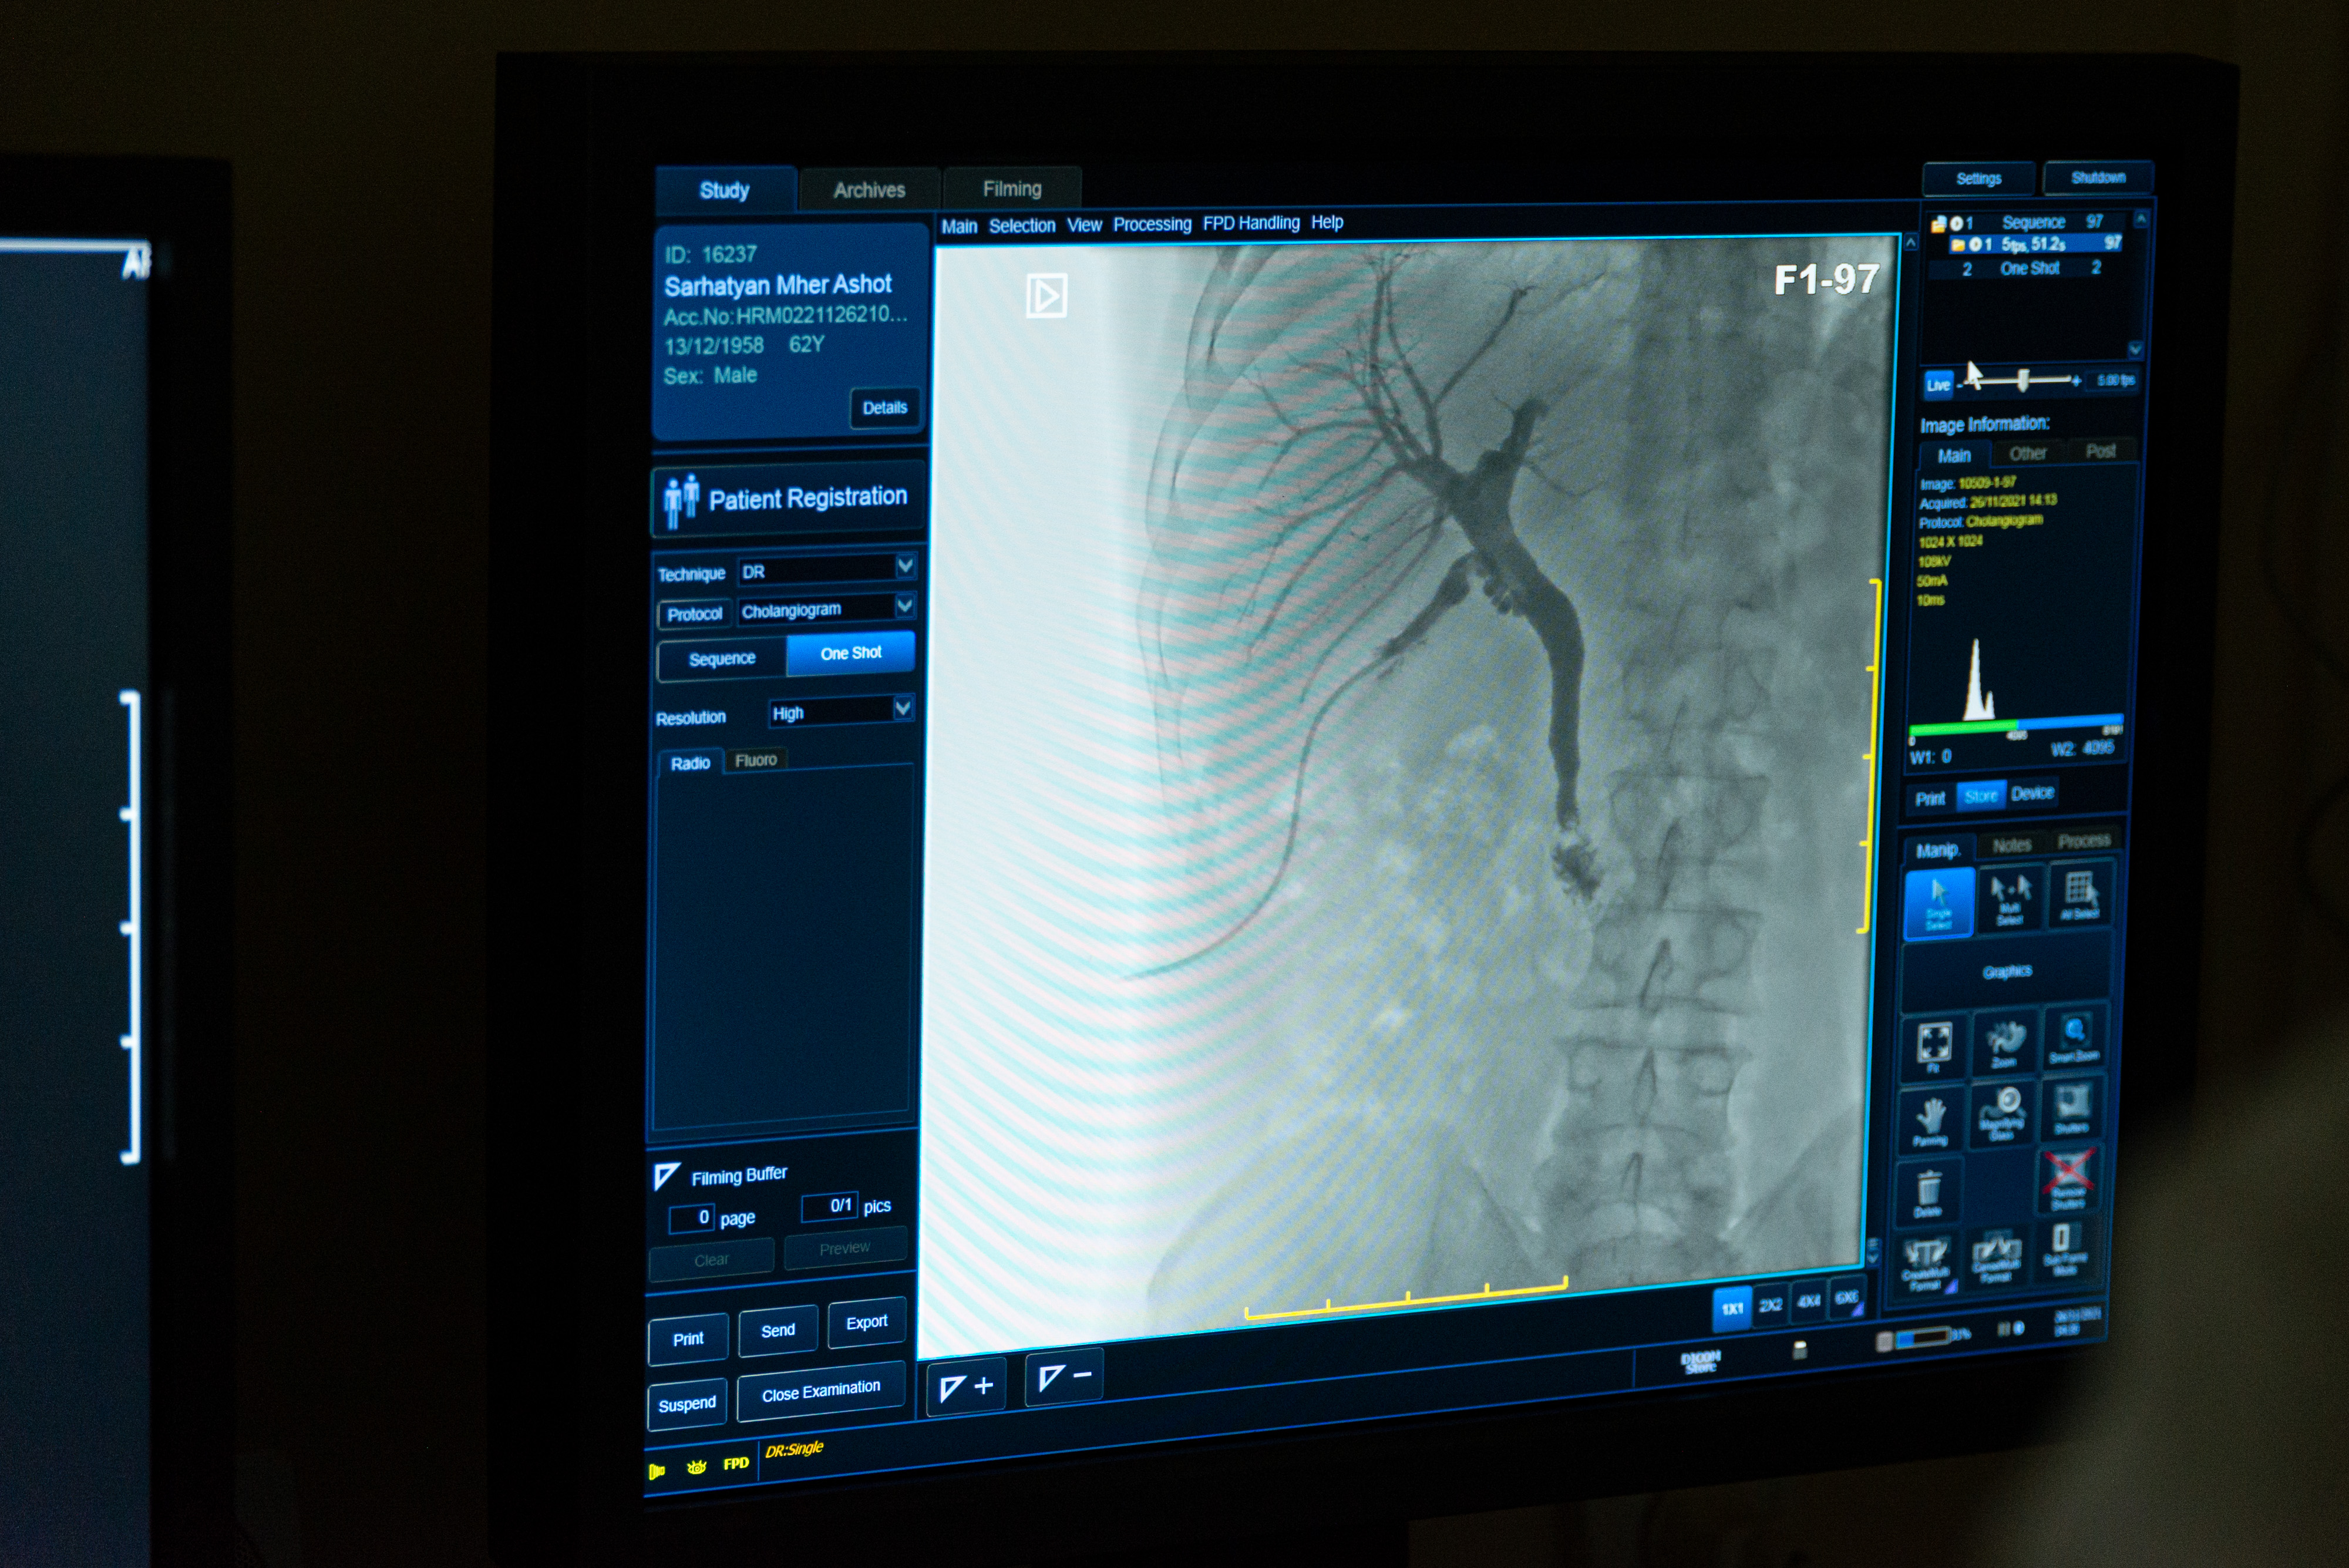

Рентгенологическая служба выполняет стандартные рентгенологические исследования органов грудной клетки, верхних и нижних конечностей (кости, суставы), таза, позвоночника, черепа, носоглотки, носовых полостей, контрастное исследование желудочно-кишечного тракта детей до 18 лет: (Динамическое исследование пищевода, желудка, тонкой и толстой кишки, ирригоскопия, ирригография, колостография, фистулография). Пациентам всех возрастных групп проводят контрастные исследования мочевыделительной системы: смешанную цистоуретрографию, ретроградную уретроцистографию, эпицистоуретрографию, цистографию после аугментации кишечным фрагментом мочевого пузыря, антеградная пиелография (нефростография), ретроградная пиелография (под наркозом совместно с урологами), внутривенная экскреторная урография. Отделение оснащено рентгеновским аппаратом Siemens с цифровым приложением, а также компьютерным томографом Toshiba.

Рентгеновское исследование